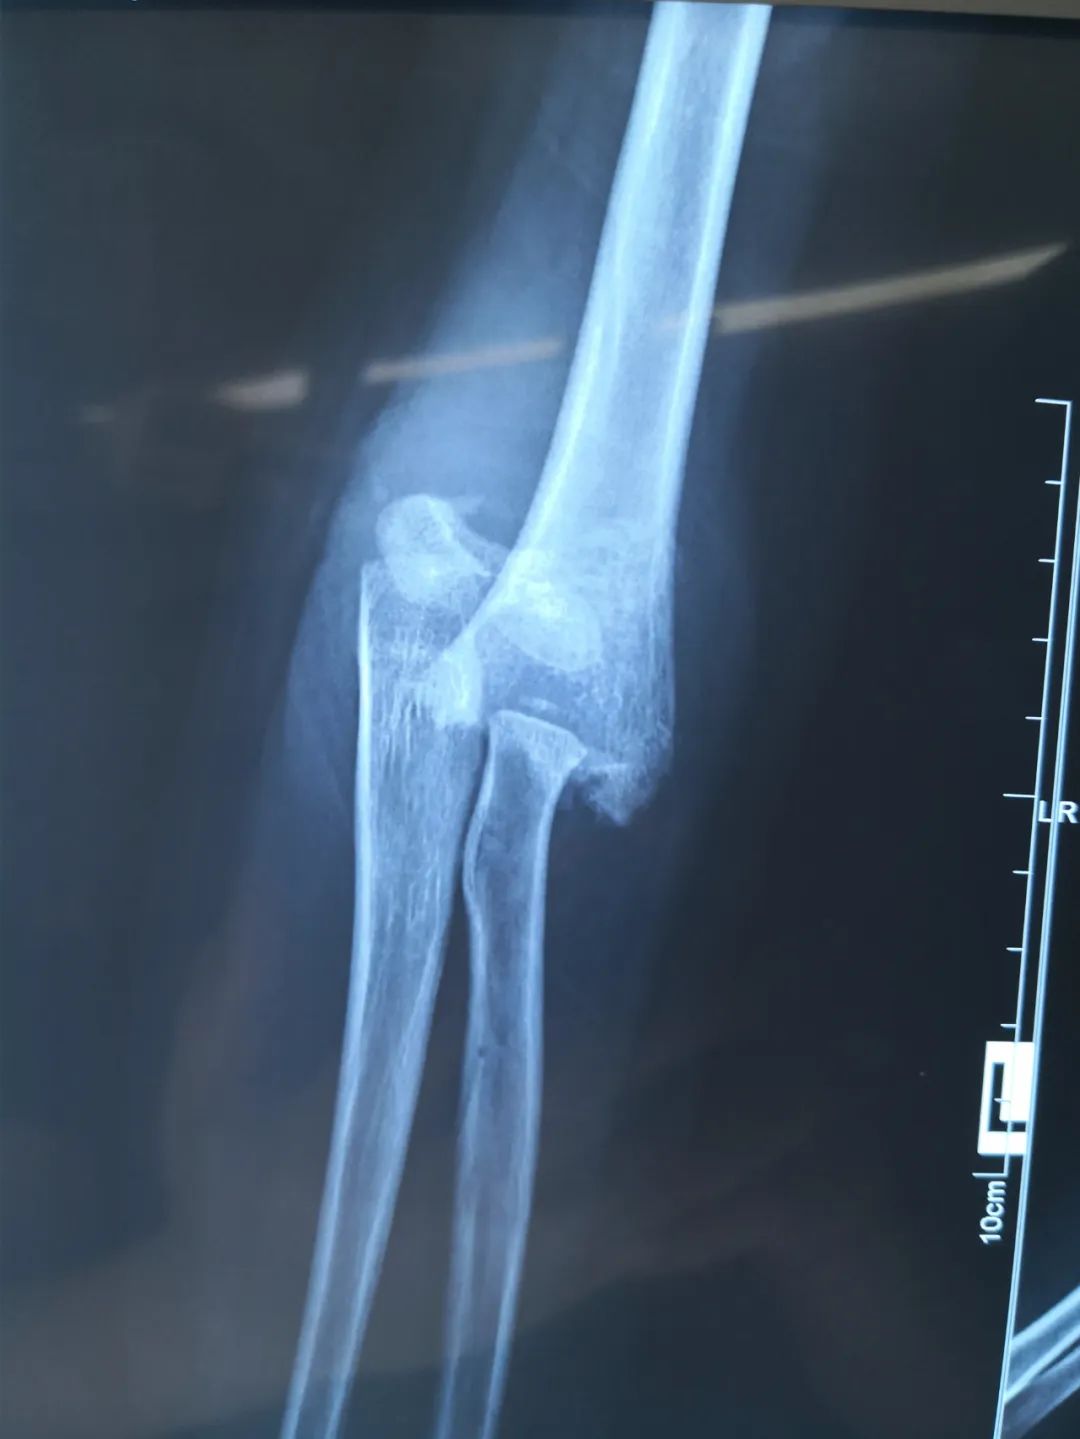

近日,淄博市第七人民医院连续接诊4例因使用平衡车摔伤的儿童,其中1例受伤较重,右侧胳膊骨折伴桡神经损伤。另2例骨折给予手法复位闭合穿针内固定。还有1例皮外伤给予清创包扎后离院。

刘法银医生介绍称,经检查,童童诊断为右侧肱骨髁上骨折,软组织挫伤重,伴桡神经损伤,给予‘桡神经探查术+切开复位内固定术’。